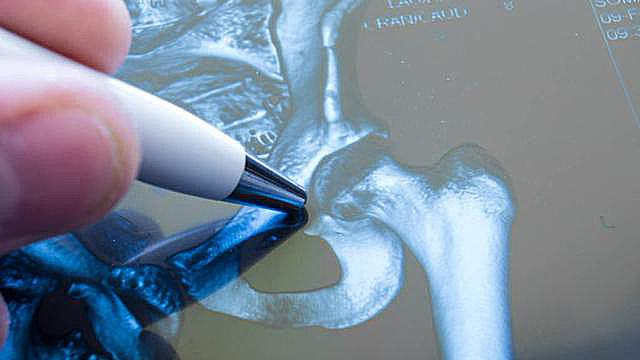

股骨颈骨折是指股骨头下到股骨颈基底的骨折,多属于囊内骨折,好发于中老年人。大多数患者存在骨质疏松症,轻微*力暴**如摔倒、扭伤等即可导致股骨颈骨折,最常见的并发症是骨折不愈合和股骨头缺血坏死。根据不同的分类标准可有不同的分型。国际上最为广泛应用的分型为Garden分型。I型,不全骨折;II型,完全骨折未移位;III型,完全骨折部分移位;IV型,完全骨折完全移位。从I到IV型股骨颈骨折越发严重,越容易发生股骨头缺血坏死和骨折不愈合。